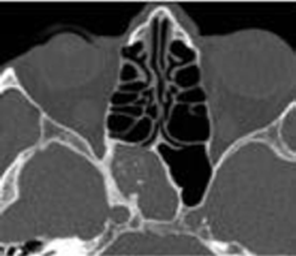

La physiopathologie des rhinosinusites repose sur l’œdème de la muqueuse qui au début est le résultat d’une implication multifac- torielle : l’inflammation – l’infection virale ou bactérienne – l’al- lergie nasosinusienne – la pollution de l’environnement – le taba- gisme actif surtout mais passif également. Cet œdème entraine un blocage et une obstruction des ostiums sinusiens (orifices de drainage). Ceblocage anatomo-fonctionnel entraîne une hypoxie muqueuse qui génère à sontour un œdème contribuant ainsi à la pérennisation de l’œdème de la muqueuse rhinosinusienne.